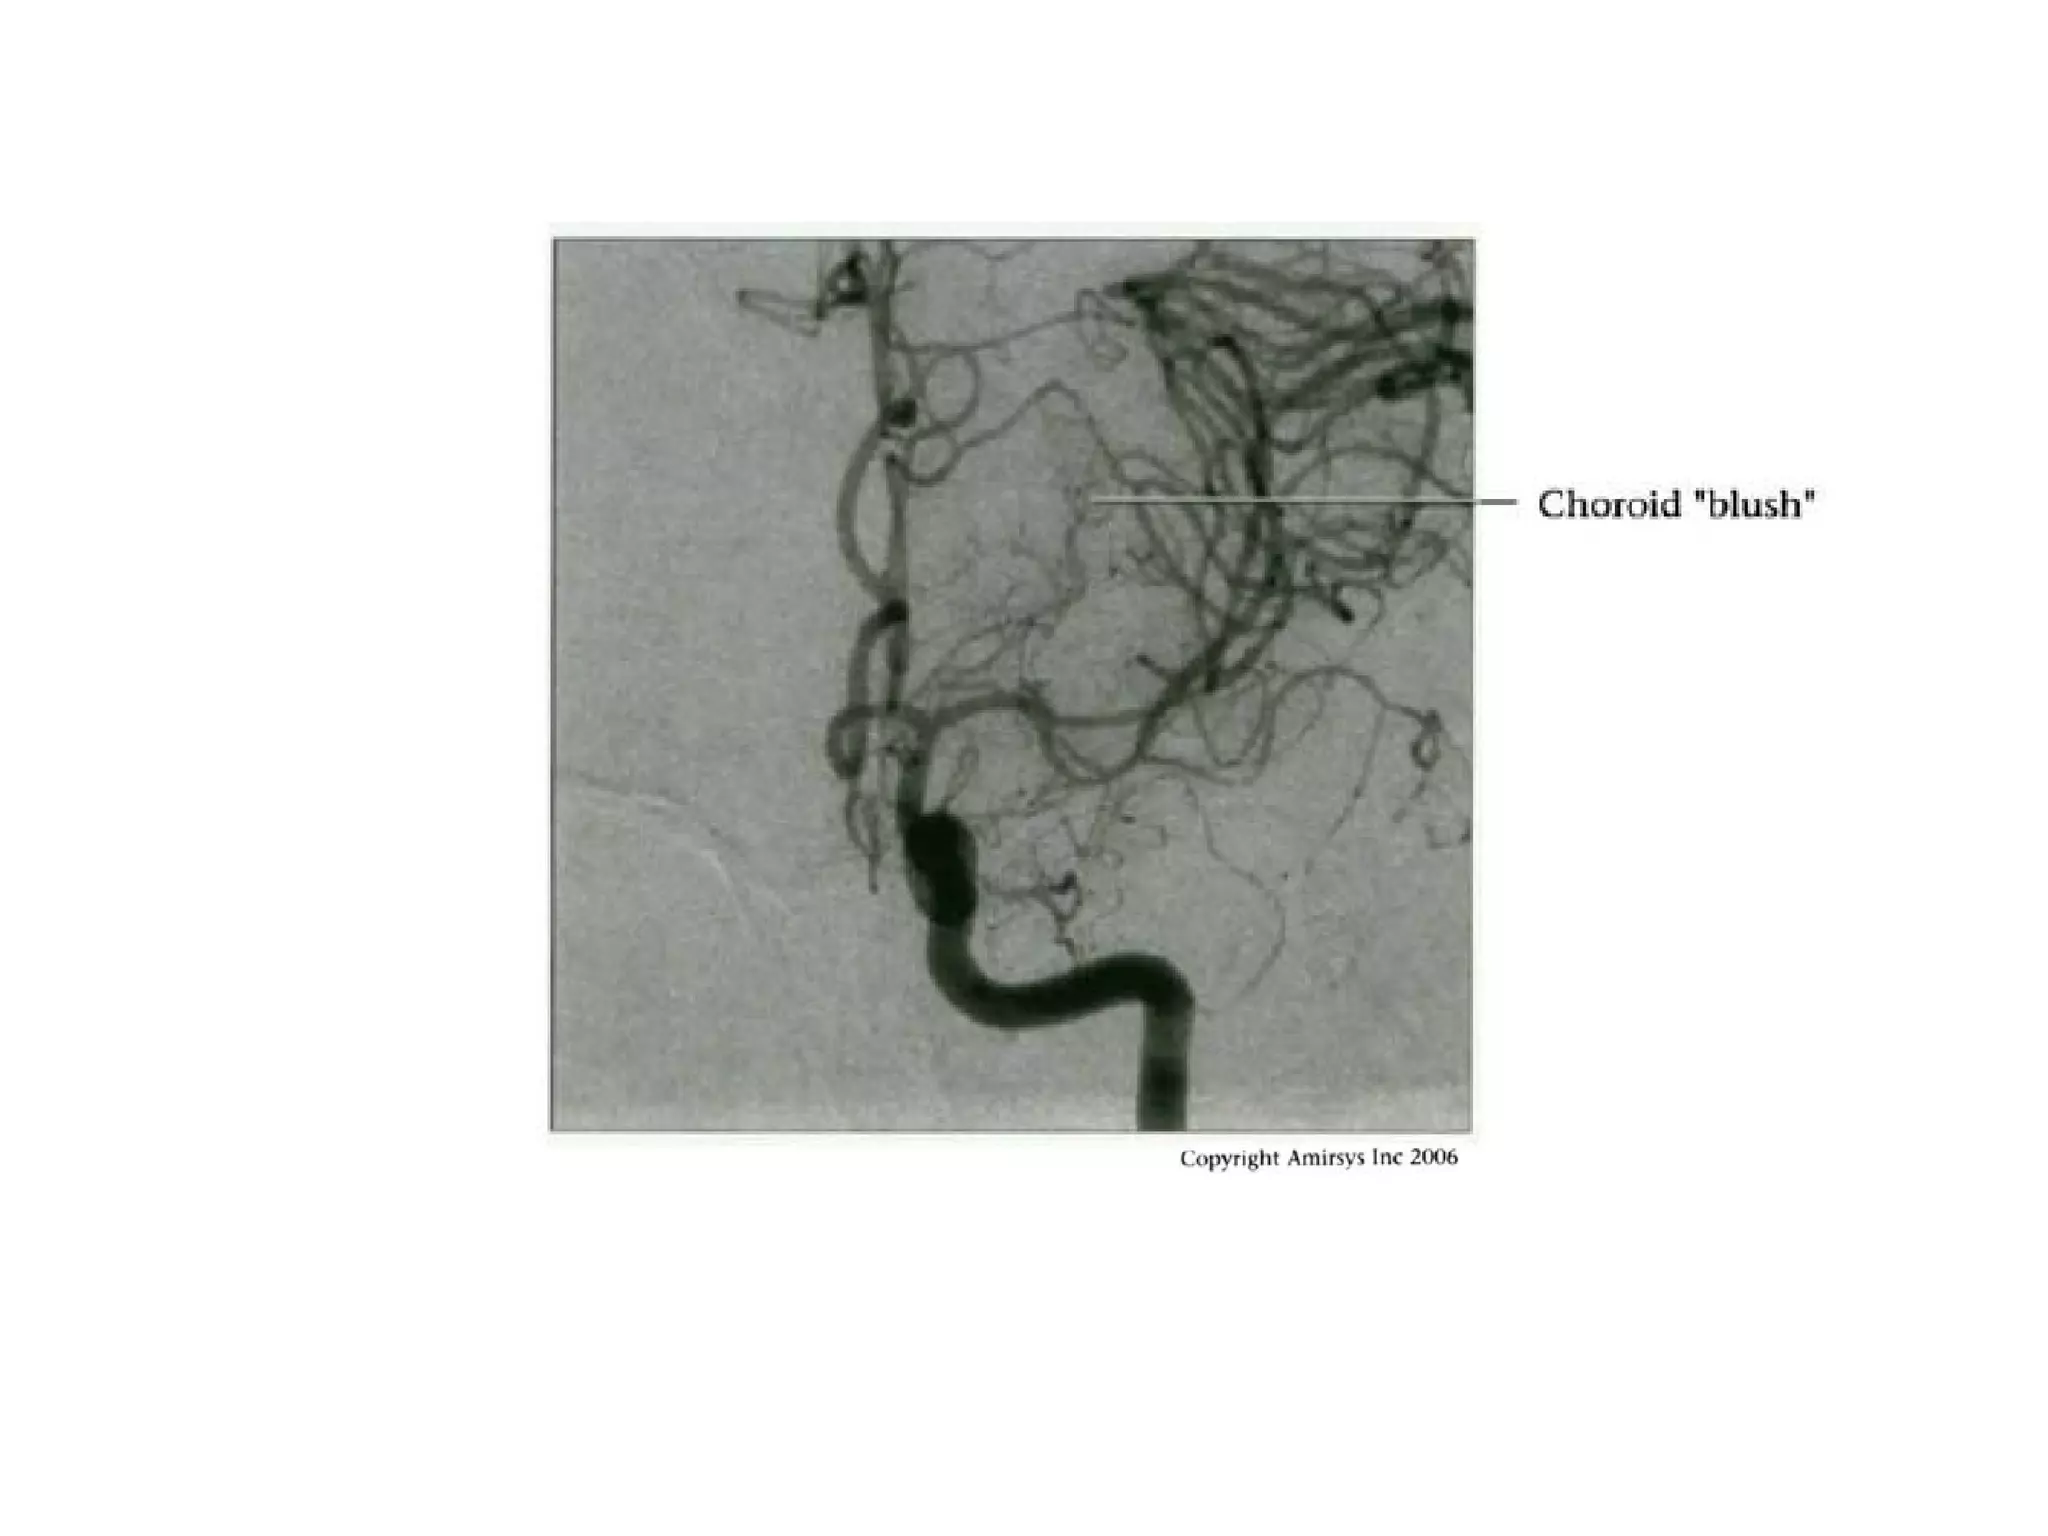

- Anterior choroidal artery (courses posteromedial,

posteroinferior internal capsule)